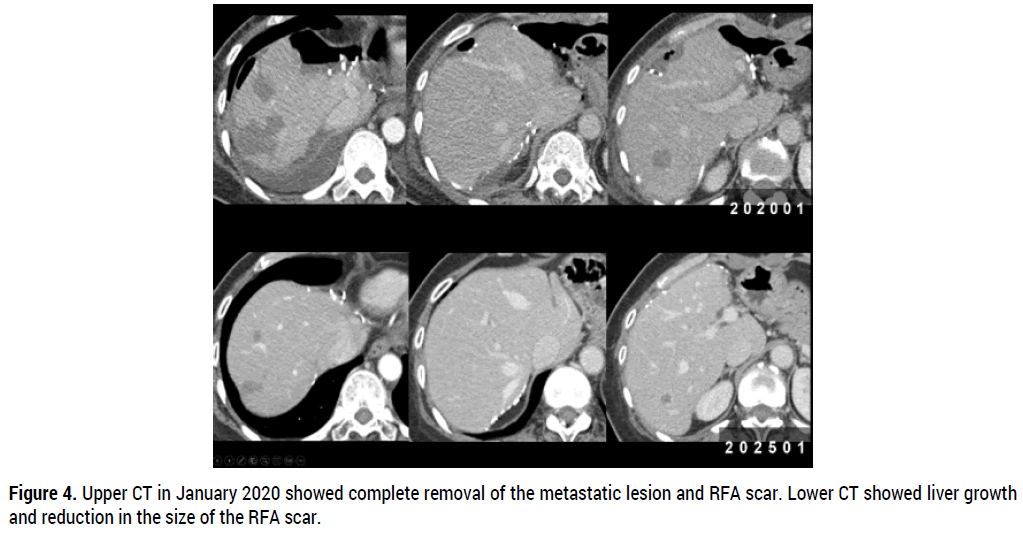

A 55-year-old female patient presented in January 2020 with 20 liver metastases (11 in the left lobe and 9 in the right lobe) (Figure 1). Previously, she was diagnosed with right-sided breast cancer with multiple life-threatening hepatic metastases in a local clinic. The patient was treated with palliative chemotherapy consisting of docetaxel and doxorubicin followed by tamoxifen, which blocks the effects of estrogen on hormone receptor-positive breast cancer. However, the disease progressed. She was referred to our surgery center and underwent a left lateral sectionectomy, partial resection of segment IV, multiple wedge resections of the right lobe, and intraoperative Radiofrequency Ablation (RFA) to ablate any remaining lesions (Figure 2, 3). The resected breast cancer cells were ER-positive, PR-negative and HER2-negative, and since then, we administered palbociclib with fulvestrant from May 14th 2020, to the present day for 5 years without recurrence (Figure 4).

Figure 4. Upper CT in January 2020 showed complete removal of the metastatic lesion and RFA scar. Lower CT showed liver growth and reduction in the size of the RFA scar.